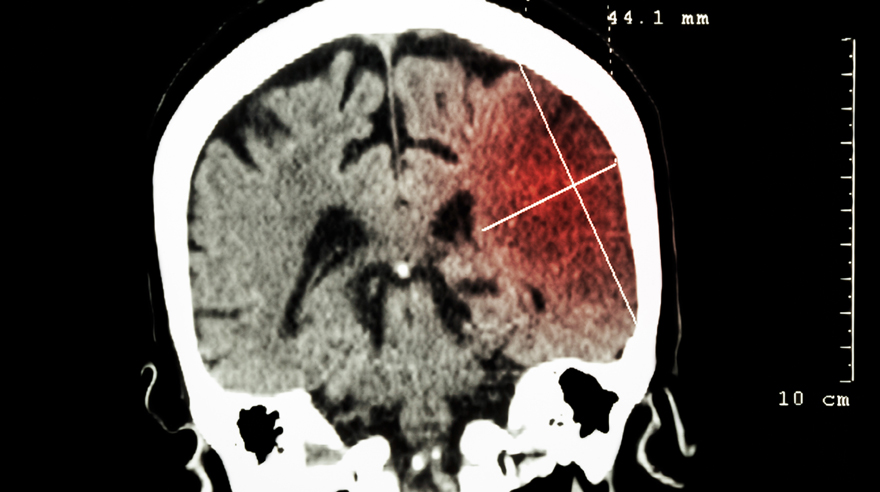

🧠 젊은 층 뇌졸중, 원인은 ‘혈관 박리’

우리가 흔히 아는 노인성 뇌졸중은

👉 동맥경화 + 혈관 막힘

근데 젊은 사람은 다릅니다.

👉 혈관 박리(동맥 박리)